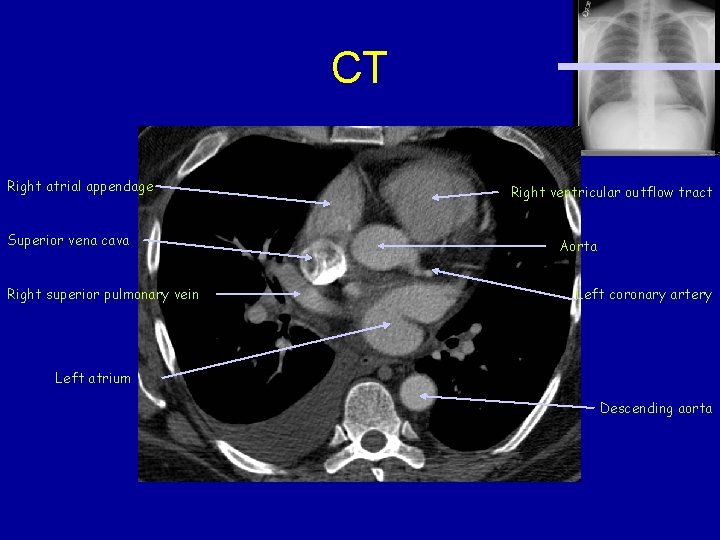

CT Right atrial appendage Superior vena cava Right superior pulmonary vein Right ventricular outflow tract Aorta Left coronary artery Left atrium Descending aorta